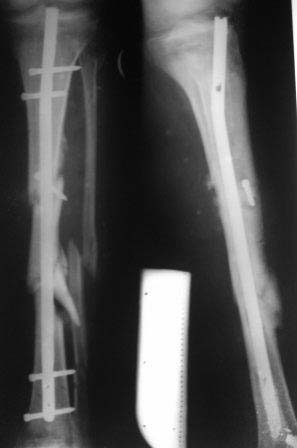

Здравствуйте, уважаемые коллеги!Больной 1976г.р. получил тяжелую сочетанную травму в апреле ,был в коме около 1 месяца. 09.05.12г.операция КДО аппаратом Илизарова в другом регионе,перелом шейки бедра пропущен. Обратился к нам сегодня для дальнейшего лечения, ходит c двумя костылями, укорочение 4см, на правой голени аппарат Илизарова в вальгусном положении, разболтанность в пр.т/б суставе,повреждение ипсилатеральное. В плане сначала БИОС б/берцовой кости после остеотомии м/берцовой и коррекции деформаций голени,после т/эндопротезирование пр. т/б сустава, Нужен совет: 1.последовательность операции? 2.или другие варианты лечения? С уважением Абдурашид. р-снимки прилагаются-от 17.12.12г.

Добрый вечер.Больной лежит на платной койке, долго ждать не можем, сегодня прооперировали: в обл. проксимального перелома открытая (разрез кожи 5см) остеотомия, репозиция, в дистальном закрытая остеоклазия,коррекция деформации.Но после введения гвоздя проксимальный фрагмент смещается кпереди, поэтому пришлось фиксировать винтом.

Р-снимок прилагается.